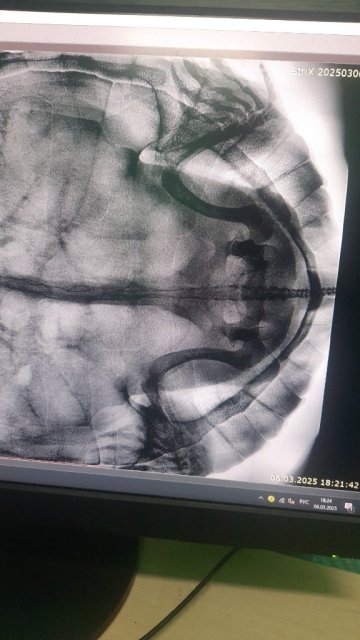

Татьяна.04 Ваше имя: Татьяна Локация: Россия, Люберцы Опубликовано: 6 марта 2025 Автор Опубликовано: 6 марта 2025 На снимке видно (не очень четко) только одно яйцо

Алексей Alex-Raduga Ваше имя: Алексей Локация: Россия, МО, Серпуховский район Опубликовано: 6 марта 2025 Опубликовано: 6 марта 2025 @Татьяна.04 так, значит пока рано, придется подождать и еще потом сделать рентген.

Татьяна.04 Ваше имя: Татьяна Локация: Россия, Люберцы Опубликовано: 6 марта 2025 Автор Опубликовано: 6 марта 2025 Яйцо большое достаточно с левой стороны, внизу А остальные через сколько сформируются, не подскажите?

Консультанты moth Ваше имя: Мария Локация: Москва Опубликовано: 6 марта 2025 Консультанты Опубликовано: 6 марта 2025 @Татьяна.04 здравствуйте! у меня черепаха к 30+ приближается, а может и больше уже и каждый год несётся, а то и по два раза по снимку яйцо правильной формы и не должно быть проблем с кладкой. Будут ли ещё другие яйца - вообще никак не угадать. В среднем 2-3 недели идёт на формирование новых.